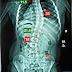

從X光片來看(圖一),該個案為胸大彎的曲線類型,33度胸椎側彎凸向右側,18度腰椎側彎,最凸點為胸椎第9節。其中最傾斜的椎體角度,分別為胸椎第四節11.5度、胸椎第十二節21.5度及腰椎第五節,兩側骨盆為左高右低,相差4 mm。觸診評估